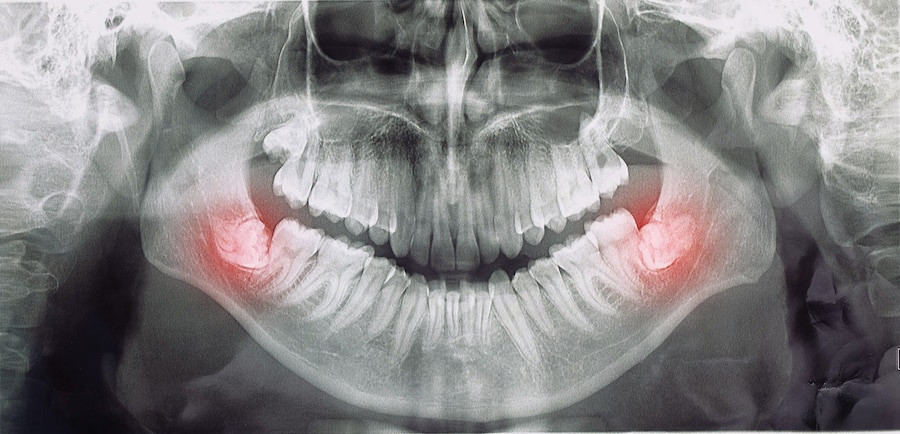

TAG: nyeri gigi

Ada 9 Artikel yang mempunyai tag "Nyeri Gigi"